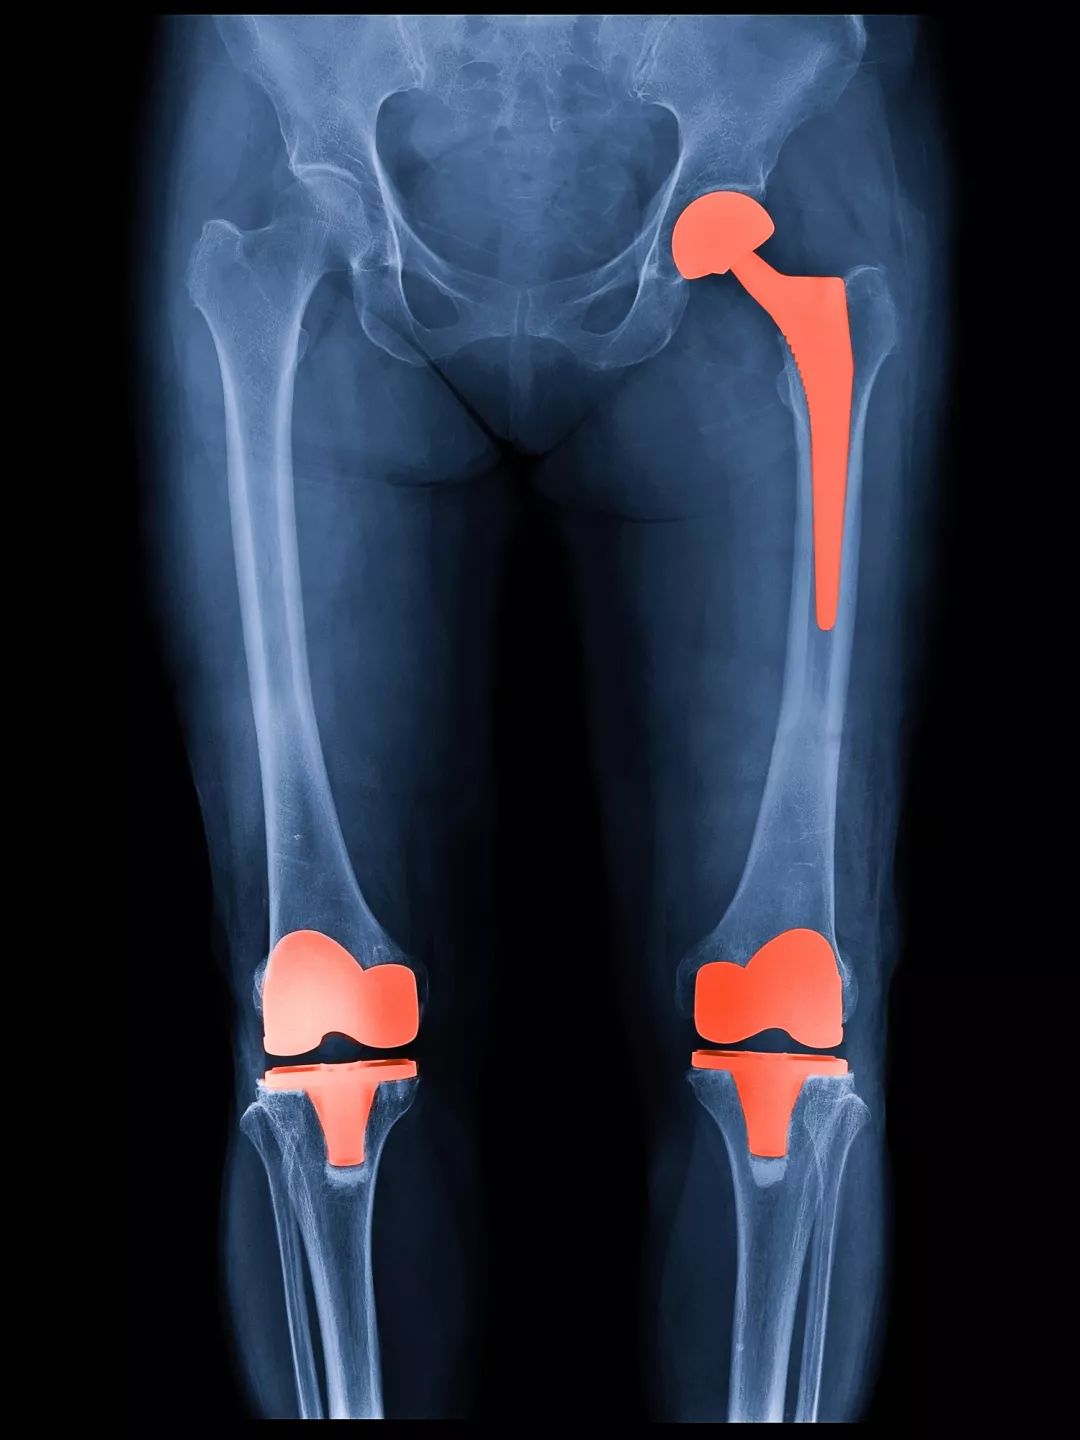

修复性治疗:包括目前还在研究中的软骨修复技术,以及应用比较广泛的胫骨高位截骨矫正力线等手术方式。

重建性手术:人工关节置换手术。包括全膝置换、单髁置换、髌股关节置换等。

在二三十年前,关节炎不管发展到什么严重的程度,都只能靠吃止痛药来忍着。逐渐丧失劳动能力,行走功能甚至生活能力;有些患者因为疼痛难忍,最终做了膝关节融合,甚至是截肢。

自上世纪八十年代前北大人民医院吕厚山院长将膝关节置换术引入国内以来,经过几十年的发展,目前这项技术已经非常成熟,全国每年光膝关节置换就要开展数十万例,成功案例不胜枚举。关节置换术也被誉为上世纪最伟大的三大医疗技术发明之一,成功解决了各种终末期关节炎、晚期股骨头坏死等原本无法解决的医疗难题。

所以说,有这种既好用又成熟的技术,并且自己的病也发展到了这一步,经济和身体允许的话,为什么不用呢?

当然,置换的关节假体是有使用寿命的,如果年龄较年轻,比如低于55岁,甚至是50岁,需要详细的评估利弊,再做选择。

30 关节炎到什么程度,需要膝做关节置换?

最重要的两个指标,大家记住:

①从x光片上看,关节炎已经进展到终末期;

②从症状上看,患者经过休息、药物等保守治疗,仍然存在严重的膝关节疼痛,严重影响生活质量。

这两者兼备,就可以让医生给你评估能不能置换了。